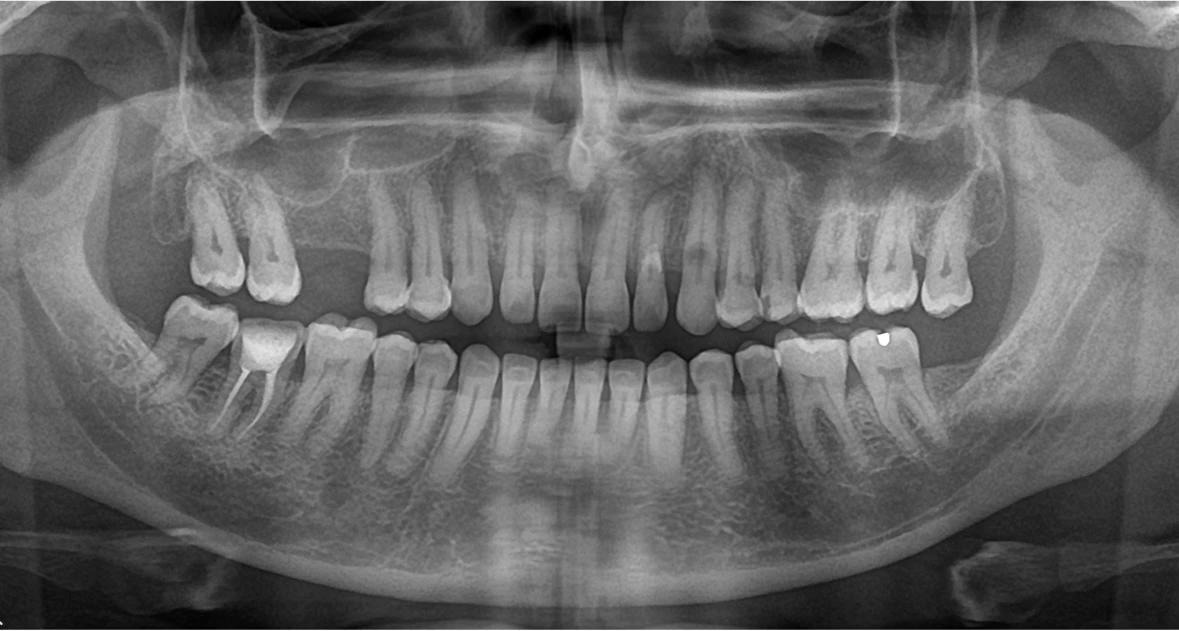

The patient reported pain and food lodgement in the lower right second premolar. No significant medical history. Due to a busy schedule, he chose Magnum Clinic for quick, expert care. The goal was to relieve pain & save the tooth via endodontic treatment.

Before the procedure, all the vital signs were observed. The cleaning and shaping of canals with rotary instruments were guided by the microscope magnification during later visits. After the obturation of the canals, a digital impression was made to fabricate the crowns. The final visit consisted of cementing a zirconia crown to restore the functionality and esthetics of the teeth.

- Day 1- consultation which includes the IOPAR followed by the initiation of the root canal treatment( access cavity preparation , partial BMP and placement of an intracanal medicament)

- Day 2 - completion of Biomechanical preparation of tooth #14 followed by obturation